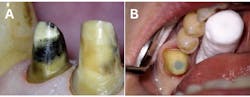

Benefits include (figure 6):32

- Diagnosis of cracked teeth

- Better visualization of pulp chamber, canal orifices during instrumentation

- Precise identification and removal of obliterations and calcifications

- Precise identification and removal of denticles

- Precise location of hidden canals/canal systems

- Perforation repair

- Removal of fractured posts and instruments

- Surgical endodontics